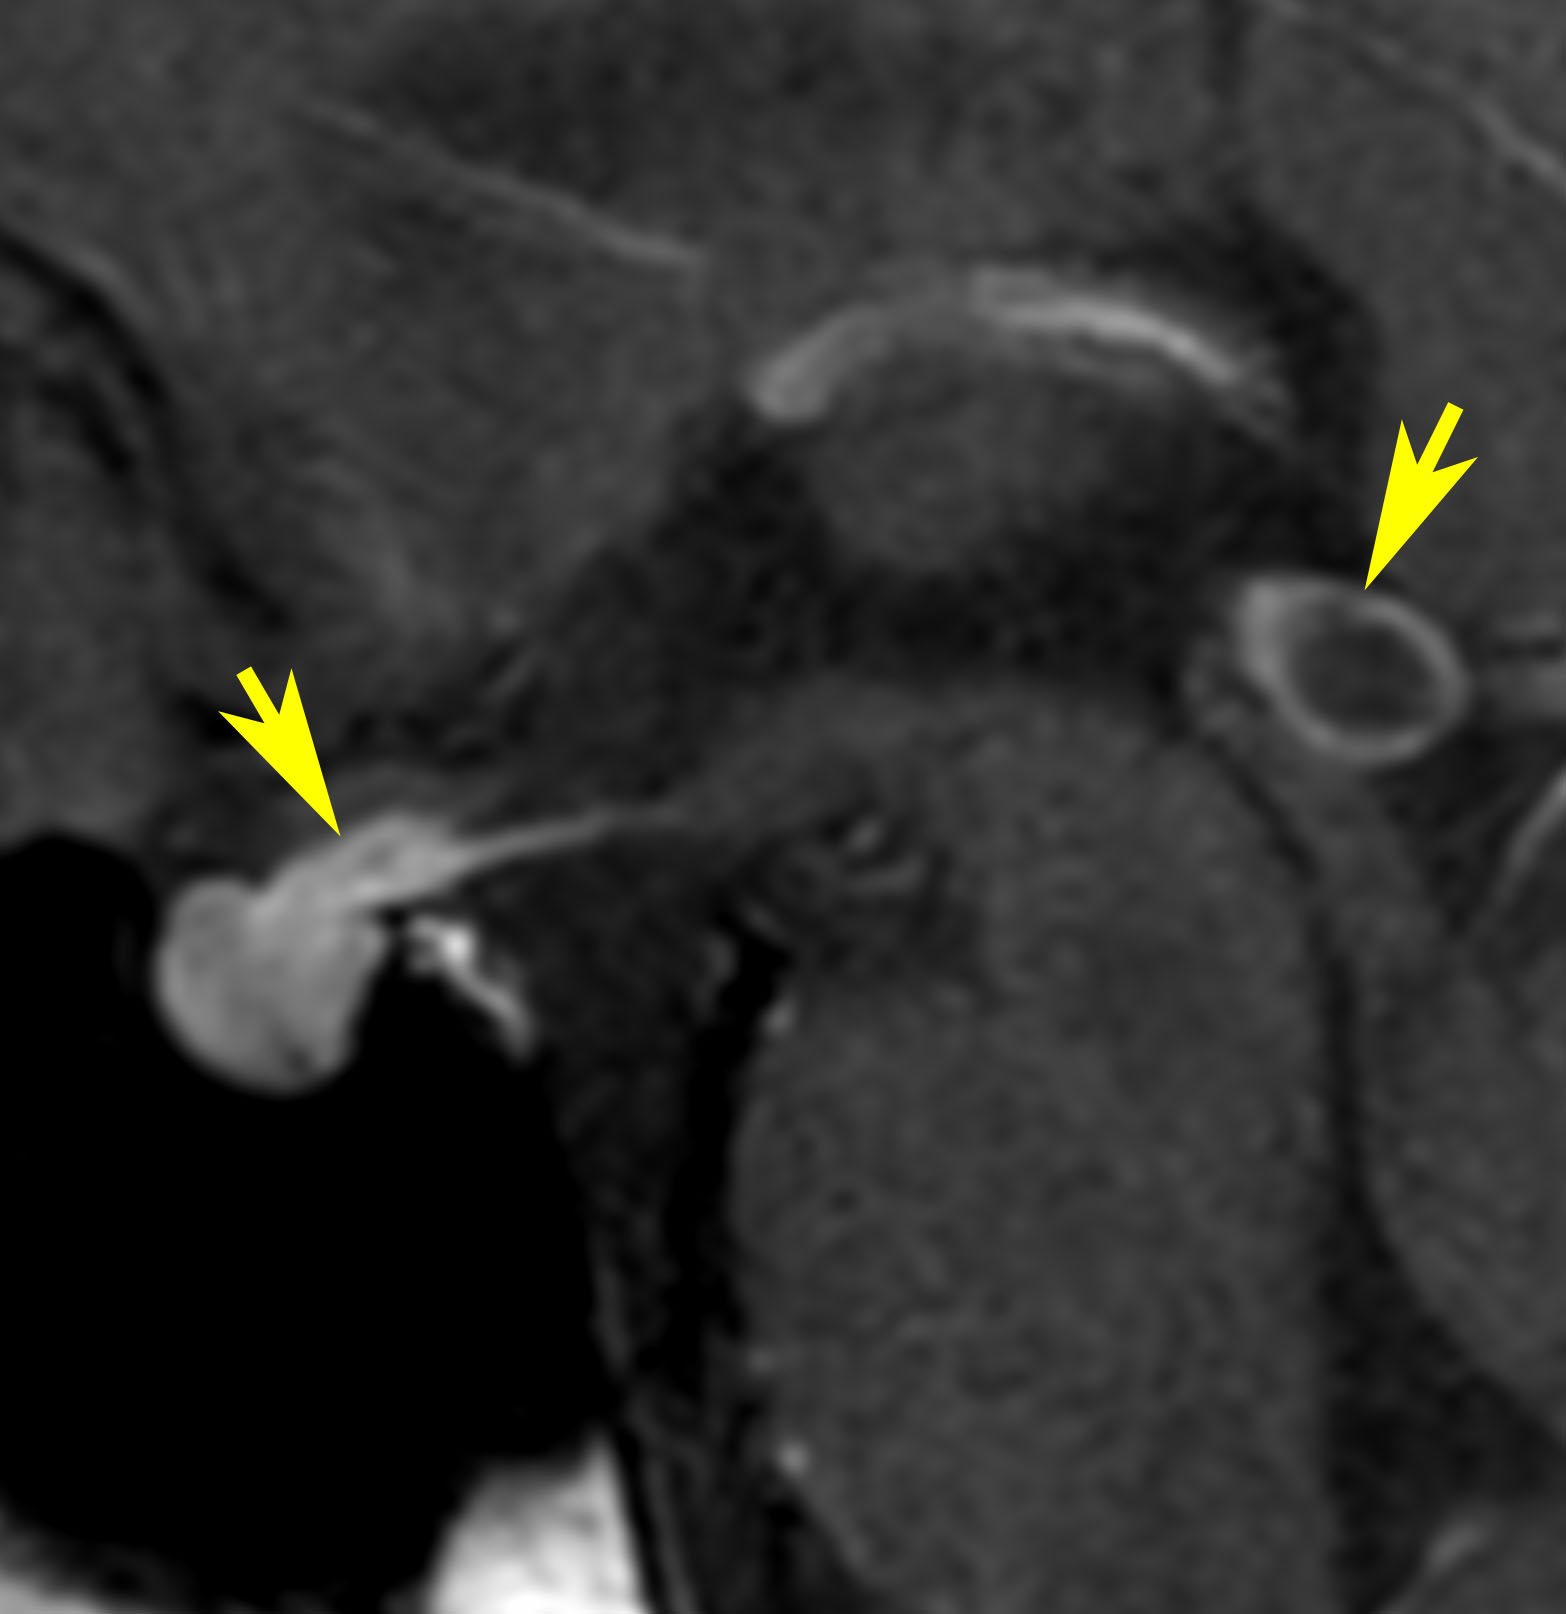

Peroperative view during endoscopic surgery in a boy with neurohypophyseal and pineal germinoma. There are numerous tiny nodules on the wall of right lateral ventricle.

These lesions are neither tumor CSF seeding nor dissemination. Germinoma cells always invades into subependymal glial tissue and spread to the whole ventricular system including the ovex. This has been called as subependymal infiltration (extension) of germinoma. Third ventriculostomy at the tuber cinereum in front of the mammillary bodies and tumor biopsy at the pineal lesion were shown.